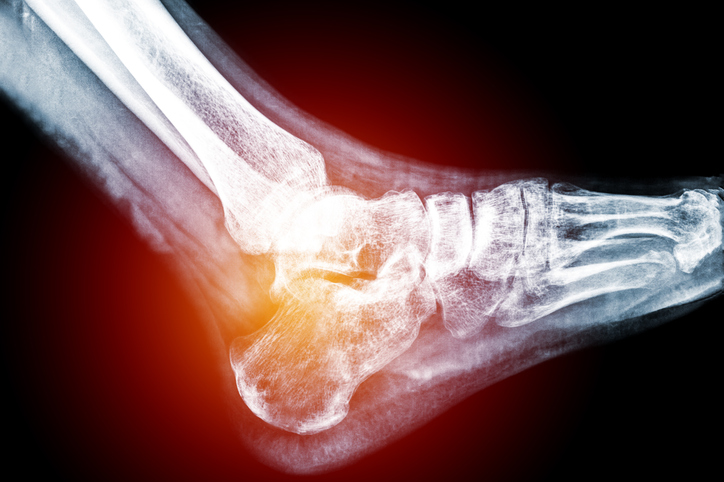

Uma lesão grave no tornozelo, que surgiu sem explicação, interrompeu a rotina, o trabalho e os planos de Rodrigo em 2023. O que começou como um simples inchaço evoluiu rapidamente para um quadro assustador, sem diagnóstico preciso e sem resposta aos tratamentos tradicionais — e foi esse cenário que levou o casal a buscar uma mudança de vida.

“Eu sempre joguei futebol desde criança. Mas em outubro de 2023, fiz meu último jogo do ano e, do nada, meu tornozelo começou a inchar. Não teve pancada, não teve lesão no jogo”, contou Rodrigo.

Com o passar dos dias, o quadro se agravou. O inchaço deu lugar a feridas abertas que surgiam sem explicação. “Começaram a estourar bolhas. Uma, duas, três… chegaram a ser 11 bolhas no meu pé, todas surgindo do nada. Eu nunca tinha visto algo assim no futebol”, relatou.

Apesar de meses de acompanhamento médico, o quadro só piorava. “Os médicos falavam em amputação. Era isso o que a gente ouvia”, disse Rodrigo.